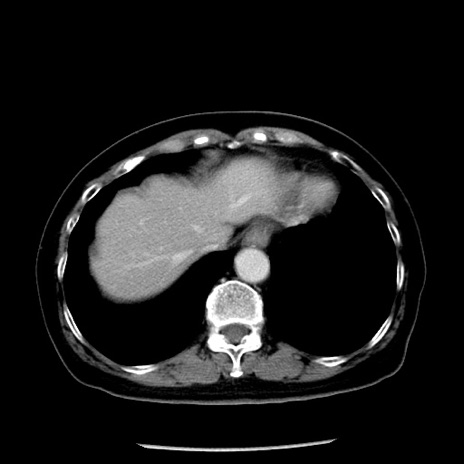

症例13(横断像)

【症例】70歳代女性

【主訴】腹痛、嘔吐

【現病歴】15時間程前(昨晩)より腹痛あり。今朝になっても症状の改善なく、嘔吐あり。腹痛も増悪あり、救急外来受診。

【既往歴】子宮癌全摘術後

【身体所見】意識清明、BP 121/72mmHg、P 74bpm、SpO2 100%(RA)、腹部:平坦・軟、腸雑音ほぼ聴取せず。下腹部・心窩部・臍左上に圧痛あり。反跳痛なし。

【データ】WBC 10600、CRP 0.15